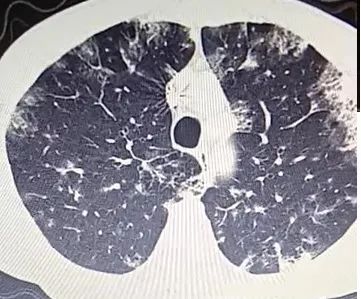

下面这个CT,乍一看,是不是毫无头绪?

然而,当病人说每天咳痰两三碗,大约200~300ml(1市斤500ml),而且是经常这样的时候,我突然眼前一亮,莫非是?

患者老人,咳嗽咳痰伴活动后气促半年,无发热、咯血。多家医院反复就诊,抗细菌感染无好转,病灶逐渐增多。

入院查体:双下肺湿罗音。

然而,患者又说:每天咳痰两三碗,大约200~300ml,不是偶尔,是近几个月,经常这样,白色,或者黄脓痰!

但是,结合患者长期大量咳痰,腺癌(细支气管肺泡癌)的诊断呼之欲出!

■ 结果,肺穿刺:粘液腺癌!